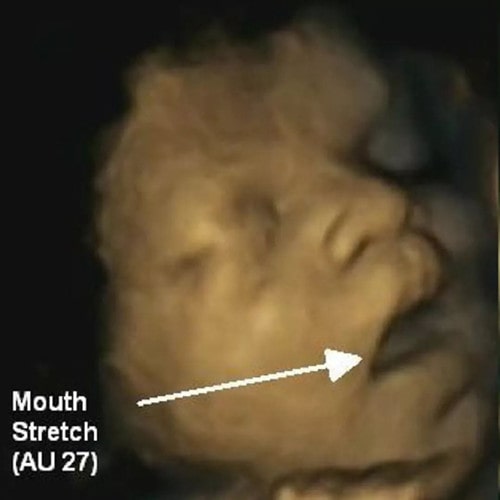

△婴儿在妈妈肚子里张嘴打嗝

孕妈一般会在27周左右,级就能感受到宝宝在肚子里打嗝。感觉就像是小节奏的抽搐,一次又一次地在子宫里微小地跳跃着。

不过,有些妈妈可能永远都不会感觉到宝宝打嗝,但对某些孕妈来说,尤其是孕后期,可能每天都能感觉到宝宝在肚子里疯狂地打嗝。